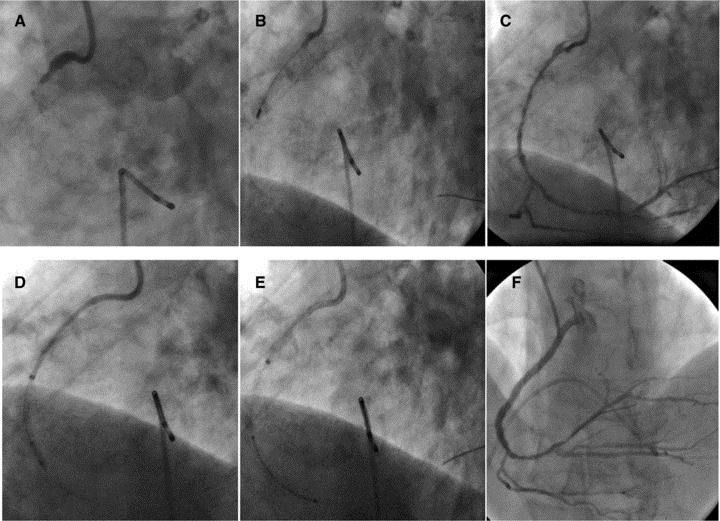

Стентирование сердца форум. Стентирование сердца форум. Первичная транслюминальная ангиопластика. Транслюминальная баллонная ангиопластика. Коронарография сосудов стентирование.

Стентирование сердца форум. Стентирование коронарных артерий. Первичная транслюминальная ангиопластика. Стентирование позвоночной артерии. Транслюминальная баллонная ангиопластика.